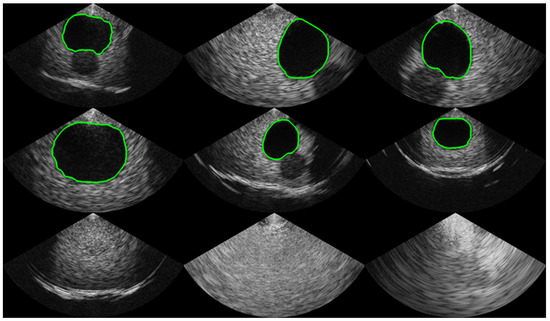

To collect a dataset with high variability, various gain and depth settings were used. The ultrasound bladder images were obtained from two tissue-mimicking phantoms: an intravesical urine volume measurement phantom (US-16, Kyoto Kagaku, Kyoto, Japan) with urine volumes of 50 mL, 150 mL, and 300 mL, and a multimodality pelvic phantom (Model 048A, CIRS, Norfolk, VA, USA). A total of 1306 images with a bladder and 2095 images without a bladder were collected. The bladder images were randomly divided into 1044 images for training and 262 images for validation, with each image labeled with a corresponding mask for the segmentation task. The images without a bladder were divided into 1675 images for training and 420 images for validation for the classification task. To capture ROIs of various sizes, the dataset was collected by randomly selecting locations with a free hand on a static phantom. To validate the size and distribution of the dataset, the accuracies on the training phase and validation phase are compared. Examples of the dataset are shown in Figure 2.

Figure 2.

Examples of the acquired dataset. The first and second rows show images with a bladder, and the green line indicates the boundary of the mask label from human labelers. The third row represents images without a bladder, indicating that the bladder was not observed.